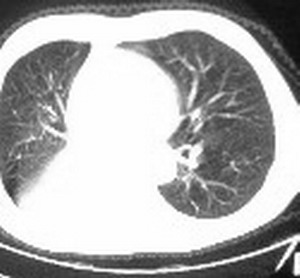

标题: CT6943:[讨论]胸部,M/67Y,体检发现。 [打印本页]

标题: CT6943:[讨论]胸部,M/67Y,体检发现。

ct值约12hu。

ct值约12hu